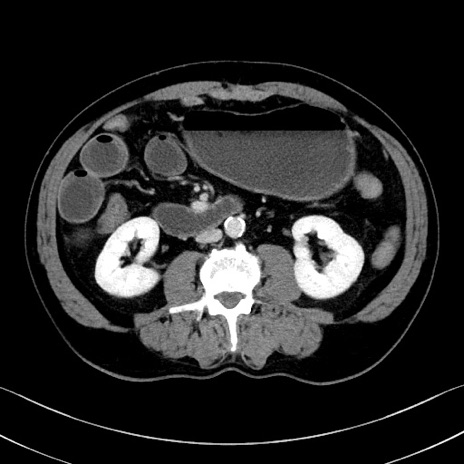

症例35(横断像)

【症例】70歳代 男性

【主訴】腹部膨満、嘔吐

【現病歴】昨日より腹部膨満感出現。本日増悪し、仙痛出現。嘔吐あり、受診。

【既往歴】糖尿病、胆摘後

【身体所見】BP 149/80mmHg、HR 74/min、BT 35.9℃、腹部:膨満、軟、圧痛なし。腸雑音減弱あり。上腹部正中切開瘢痕あり。

【データ】WBC 13500、CRP 1.72